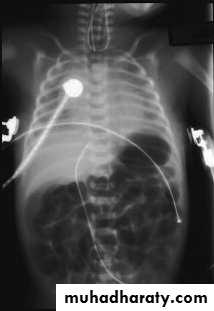

Diagnosis:-- CXRo Air & fluid filled loops of bowel in the chest.o Paucity of intestinal gas in the abdomen.o Mediastinal shift (heart shifted to the right).o Tip of NG tube seen in the chest.